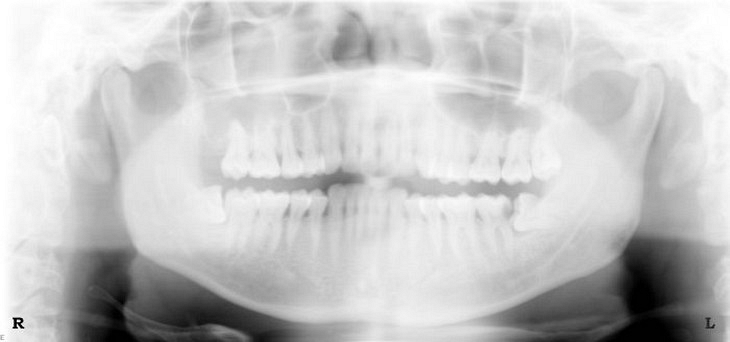

At Hobsonville Point Dental we have both intraorol digital radiography and extraoral full mouth digital x-rays. With intraoral digital x-rays, a sensor or digital plate is inserted into your mouth to capture an image of your teeth. For extraoral full mouth digital x-rays, to capture a complete image of your jaw, patients instead stand in a scanning x-ray – orthopantomogram (panorex). It’s a quick, convenient and very efficient process to almost immediately capture an image of your oral health.

Here are examples of digital dental radiography